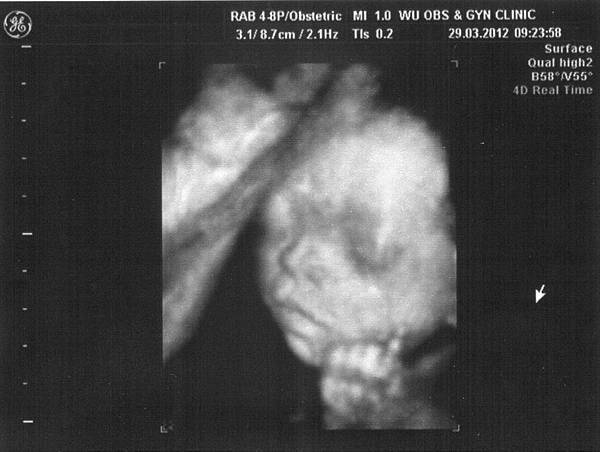

雖然這次不是產檢,但還是有機會看到小寶貝的模樣

除了還是雙腳閉閉不讓我們看個啾竟之外,

還一手遮住臉很害羞的模樣,

寶寶~你真的好害羞喔,跟媽咪一樣啦(羞)